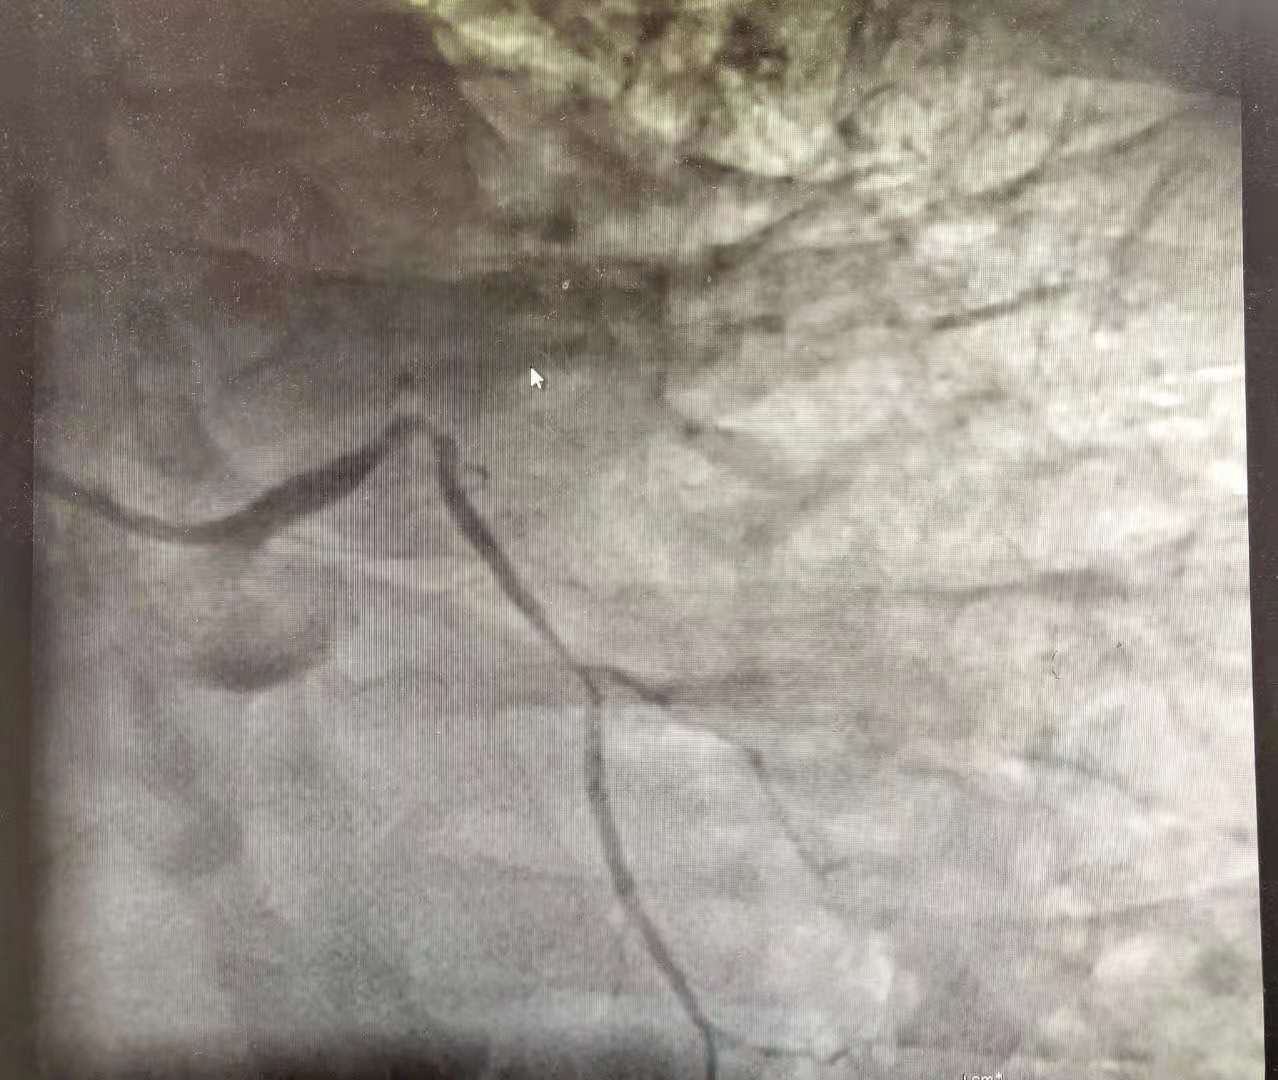

我通知手术室提前做好准备,立即护送患者手术。由于患者严重的低血压状态,我们率先植入了心脏辅助装置(IABP)帮助心脏跳动,降低术中猝死的风险。然后迅速进行冠状动脉造影……

我的疑惑解开了,但是后背也立刻泛起一股凉意:左侧的3根主要心脏血管(前降支、中间支、回旋支),只剩下1根回旋支!而这根血管开口也能看到血栓、接近堵死!

回想心电图表现,我们确定:此次急性心梗是由于中间支新发堵塞造成;而患者以前确实得过大面积心肌梗死,那根闭塞的前降支就是证明!原来患者2年来饱饭后反复出现“上腹痛”根本不是胃病,而是被“误诊”的心绞痛甚至心肌梗死!